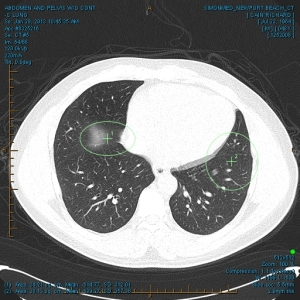

“My family and I have been the subjects of Government funded human research and/or hate crimes. These crimes are being covered-up by using the words National Security. The fact that my two minor children have the same and/or similar devices in their little bodies speaks for themselves. My sons were ages 3 and 4 when the discoveries took place. Their x-rays, blood & urine analysis present the true facts. The devices can only be introduced into the body, while being in a medical facility. All three of us were patient of the same defendant hospital.

“The CD-ROM from CCAI depicts the same images that are attached. I will bring the 01/03/2012 Simonmed Imaging CT scan which also depict foreign objets in the heart and chest.”

“Please take a look at both X-rays. Superimpose the foreign objects AKA EKG clamps and you will find that they are the same devices. when have you ever seen an EKG clamp place sideways in the abdomen? Both x-rays have been confirmed by Radiologist Louis Teresi as having foreign body reactions in the abdomen, right and left flanks.

“The obvious implant in the 2012 x-ray stands out from the others, because it at the time had not embedded into my flesh (heart).”